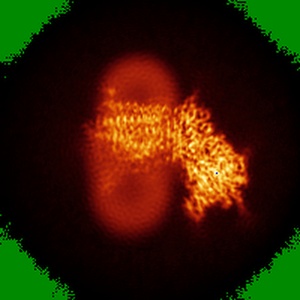

CryoEM structure of human PS2-containing gamma-secretase

Single-particle3.4 Å